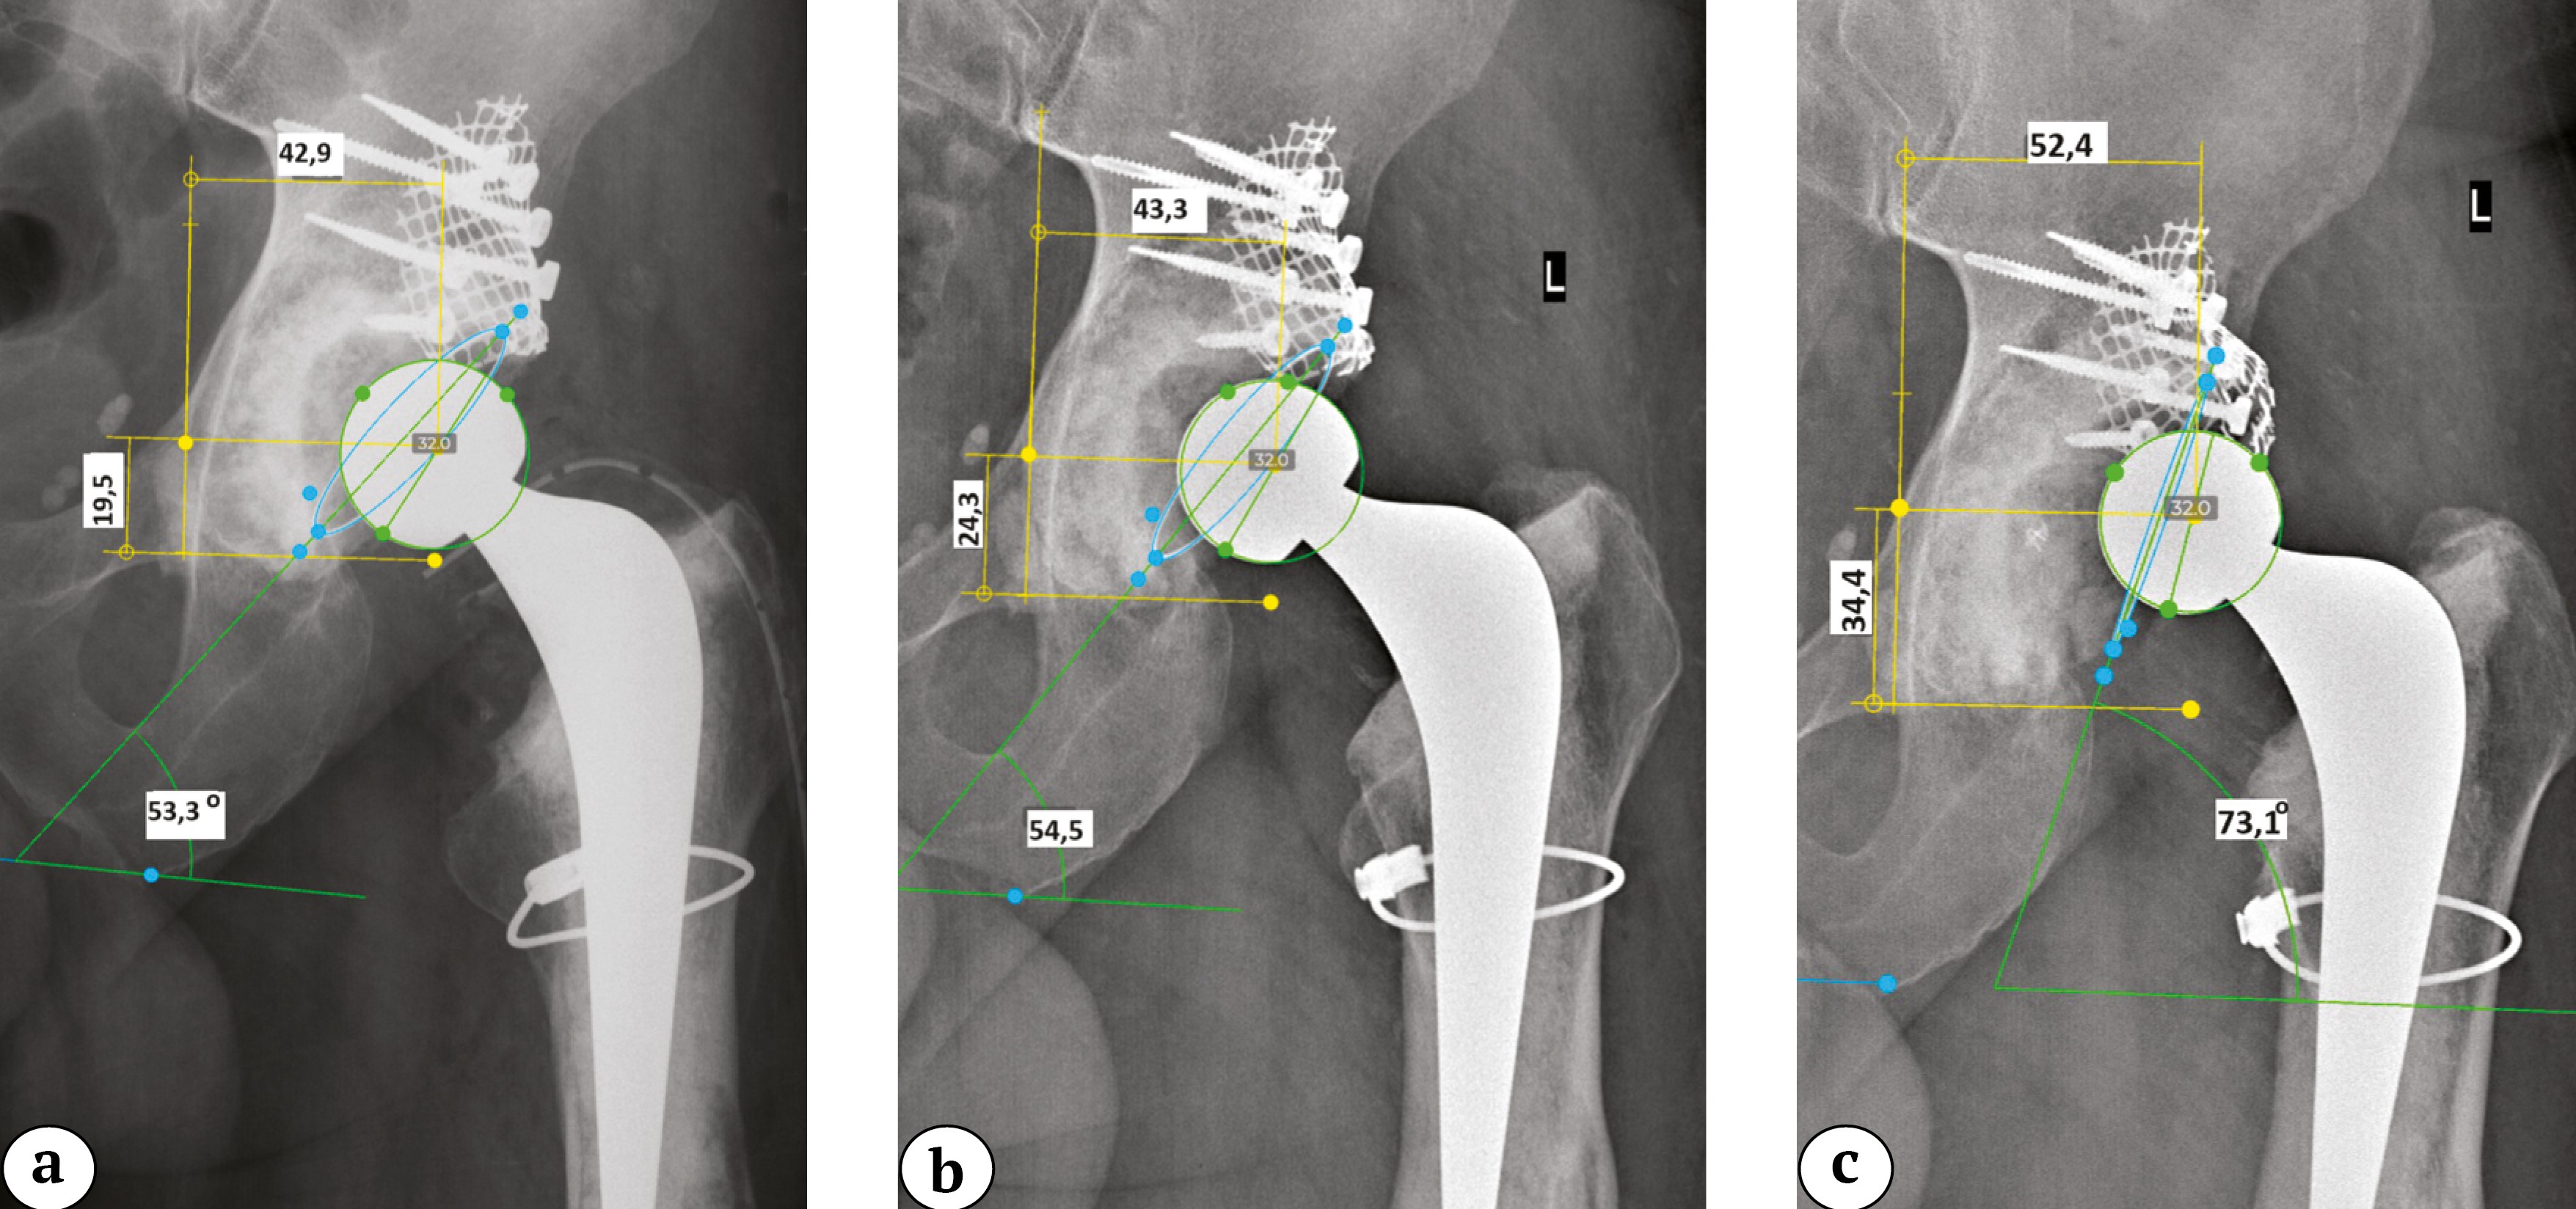

Для оценки рентгенологической динамики выбраны снимки, выполненные непосредственно после операции, через 1 год и на последнем контрольном осмотре через 5 лет с момента операции, на который пациент явился с жалобами на боли в области левого тазобедренного сустава (рис. 9). Функциональная оценка по модифицированной шкале HHS на момент последнего осмотра составила 53 балла. При оценке рентгенограмм в динамике после ревизионного эндопротезирования отмечается постепенное смещение центра ротации краниально до 14,9 мм и латерально до 9,5 мм, увеличение инклинации и изменение антеверсии тазового компонента (табл. 4). Несмотря на отсутствие рентгенологических линий просветления на границе интерфейсов данная миграция тазового компонента в совокупности с болевым синдромом была расценена как расшатывание тазового компонента.

Рис. 9. Клинический пример миграции тазового компонента с развитием расшатывания у пациента 2: a — после операции; b — через 1 год; c — через 5 лет (смещение центра ротации проксимально и кнаружи, увеличение инклинации, уменьшение антеверсии)

Figure 9. Clinical example of the pelvic component migration with subsequent loosening: a — after surgery; b — in 1 year; c — in 5 years (shift of the rotation center proximally and outward, increased inclination, decreased anteversion)

Показатель | После операции | Через 1 год | Через 5 лет | Δ |

Расположение центра ротации по оси Y, мм | 19,5 | 24,3 | 34,4 | 14,9 |

Расположение центра ротации по оси X, мм | 42,9 | 43,3 | 52,4 | 9,5 |

Инклинация, град. | 53,3 | 54,5 | 73,1 | 19,8 |

Антеверсия, град. | 13,6 | 12,6 | 2,8 | 10,8 |